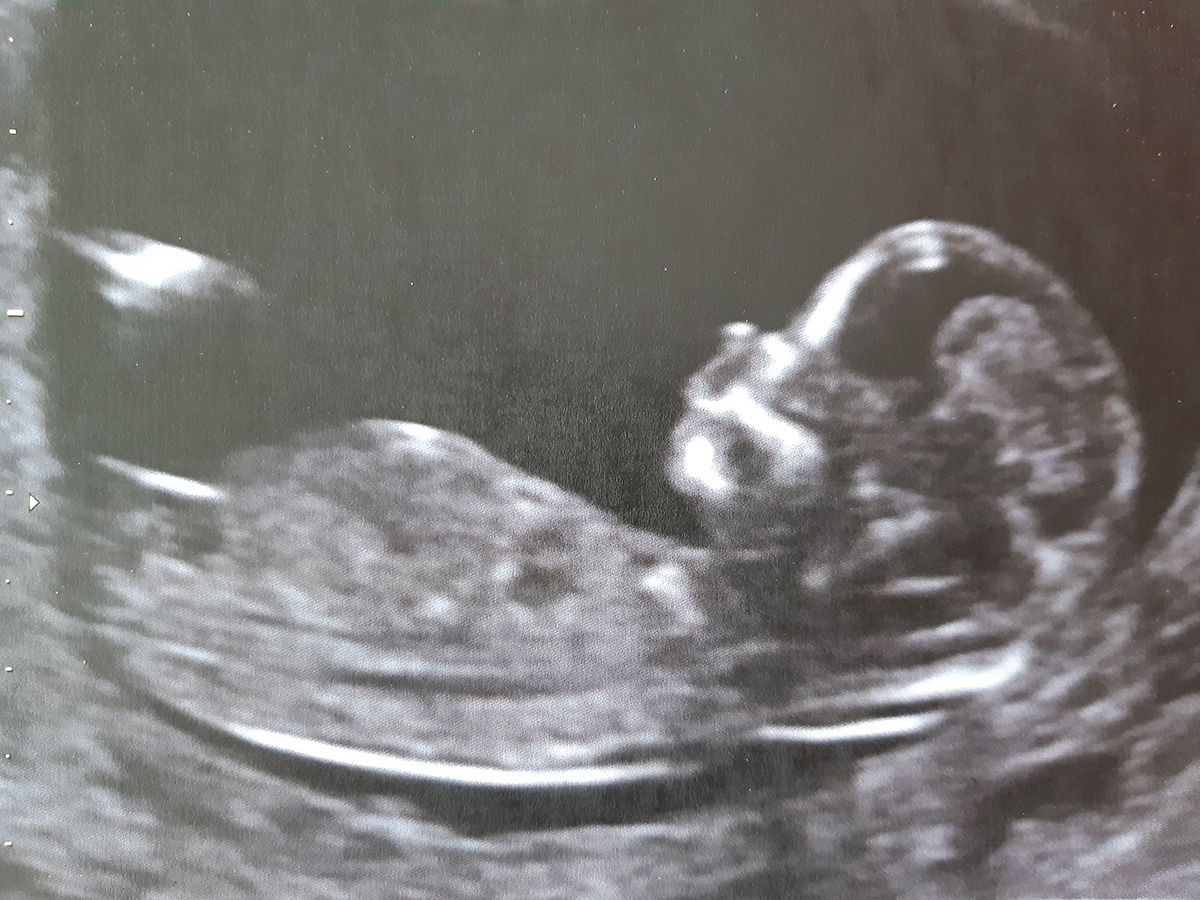

- L’échographie de datation, autrement appelée « échographie précoce », réalisée idéalement entre 7 et 9 SA (semaines d’aménorrhée, c’est-à-dire le nombre de semaines écoulées depuis le 1er jour des dernières règles), permettant de vérifier la bonne vitalité de l’embryon, d’identifier précocement les éventuelles grossesses gémellaires et de déterminer la date provisoire du début de grossesse

- l’échographie du 1er trimestre vers 12-13 SA, au cours de laquelle la datation sera définitivement réalisée, ainsi que la mesure de la clarté nucale de votre bébé dans le cadre du dépistage de la trisomie 21 (non obligatoire mais qui vous sera systématiquement proposé ce jour-là).